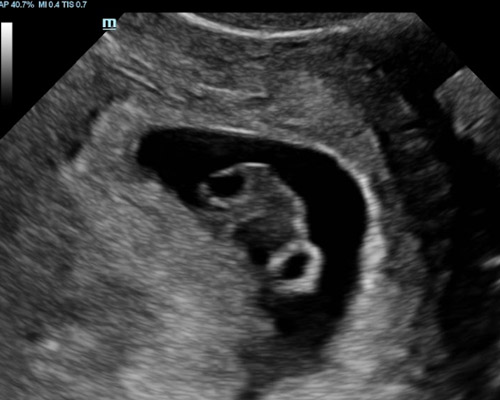

A viability scan near Wakefield is typically carried out between 6 - 12 weeks. It uses ultrasound imaging to assess how things are progressing in the early stages. During the appointment, the sonographer checks that the pregnancy is located correctly, looks for a visible heartbeat where possible, measures the embryo to estimate timing, and confirms whether there is one baby or more.

For many families, this type of early pregnancy scan Wakefield provides important reassurance. Seeing a heartbeat for the first time can be a meaningful moment and helps confirm that everything is developing as expected.

- A 2D ultrasound to confirm an intrauterine pregnancy

Sometimes it may be needed to perform a Transvaginal (Internal) scan for clear imaging in addition to abdominal scan, this involves inserting a thin probe into the vagina. It is safe and your consent will be obtained beforehand.